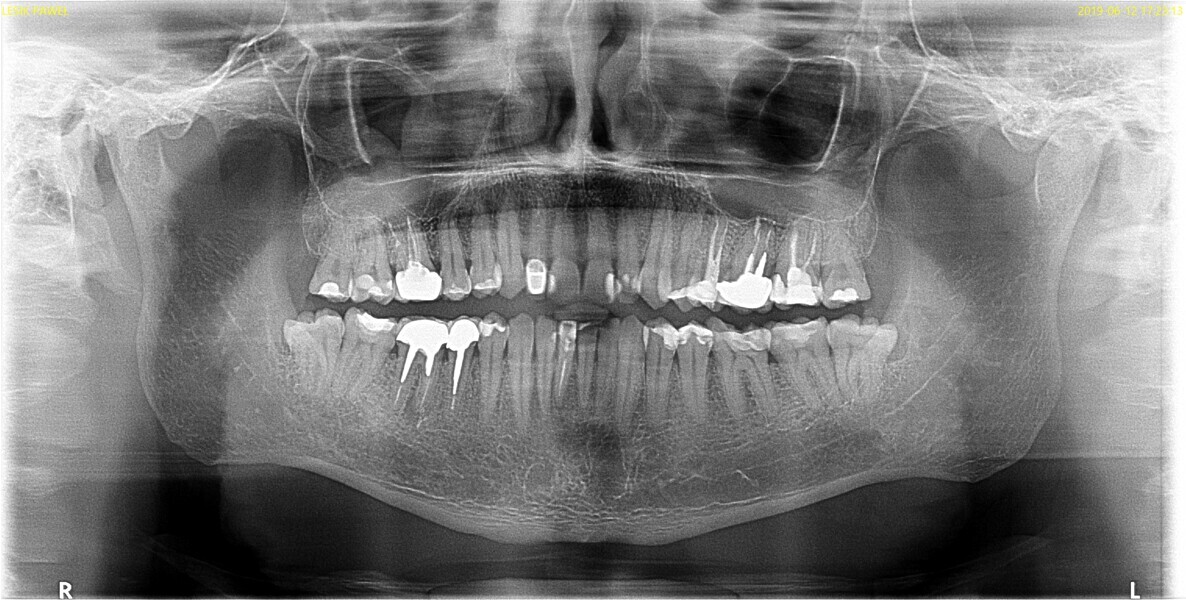

Fig. 1.

The patient was referred to Dr Witkowski’s dental office for endodontic treatment of teeth #31 and 41 (Fig. 2). After examination, endodontic treatment was performed (Fig. 3). In tooth #41, the access cavity was done by the referring dentist (Fig. 4a). In tooth #31, the access cavity was designed and performed (Fig. 4b). After this step, preparation of the canal space was done, in tooth #41 up to 25/0.04 and in tooth #31 up to 20/0.04 with VDW.ROTATE (VDW; Fig. 5). The next step was the irrigation protocol, which was performed with an Er,Cr:YSGG laser (BIOLASE) at 1.5 W and 100 Hz in both teeth. The canals were prepared for obturation. In tooth #41, obturation was done with a single point and CSBS, and in tooth #31, the piston technique was performed (Fig. 6). A control radiograph was taken immediately after the treatment (Fig. 7). Healing of the lesion was visible on the follow-up radiograph performed six months after the treatment (Fig. 8).

Fig. 7.

Fig. 8.